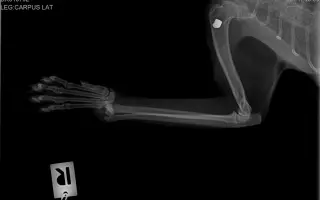

Volám sa Zalina Kumyková a dočasne sa starám o Murku — malú mačičku, ktorá sa ku mne dostala po ťažkom zranení. Jej predná labka bola v minulosti zlomená, no bez potrebnej liečby. Kosť jej zrastla nesprávne, čo jej dnes spôsobuje veľkú bolesť pri každom kroku.

Murka je ešte mladá, láskavá a neuveriteľne trpezlivá. Aj napriek zraneniu ostáva milým a prítulným tvorom, ktorý sa nikdy nevzdáva. Veterinári potvrdili, že jej stav je riešiteľný — deformovaná kosť sa dá chirurgicky upraviť.

- odbornú operáciu prednej labky (korekčná osteotómia),

- röntgenové vyšetrenia pred a po zákroku,